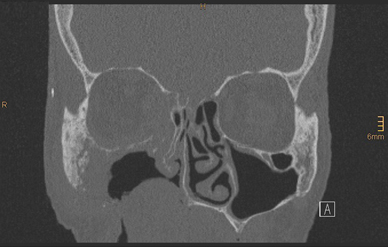

Fig. 8

Postoperative computer tomography scan showing the bony reconstruction of the zygomatic contour and the maxilla and partial reconstruction of the bony orbit

Bild vergrößern